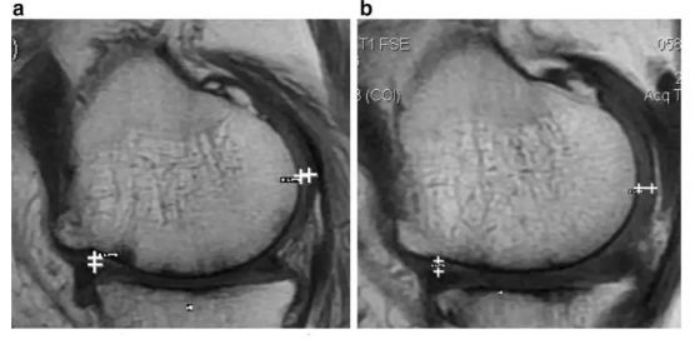

·研究结果:关节内注射骨髓间充质干细胞6个月后,,,,疼痛、、、、功能状态和步行距离均提高。。。6名治疗组中3名患者在治疗前后的MRI比较可以看出,,该治疗对于改善软骨厚度,,,,修复组织延伸超过软骨下骨,,,,以及减少软骨下骨的水肿是非常显著的。。。

下图a示意治疗前软骨,,,,b为治疗后6个月软骨,,,,箭头所示为软骨修复位置。。

如上图所示,,,左图为治疗前,,,右图为治疗后,,白色“+”处示意软骨增厚。。